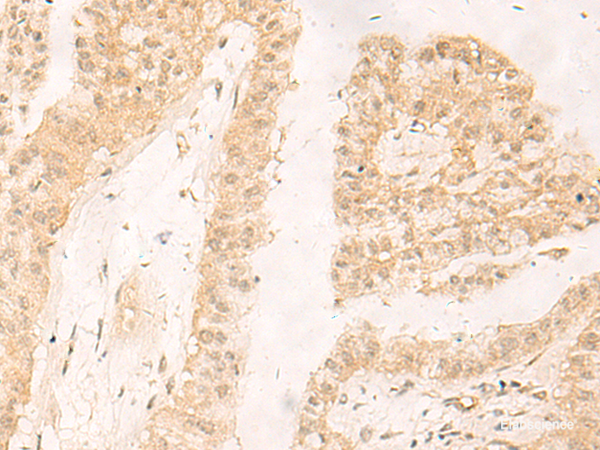

Product information "Anti-RBX1"

| Application: | IHC, ELISA |